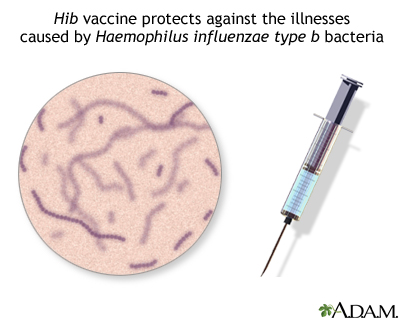

- Haemophilus influenzae type b (Hib, a cause of meningitis)

Haemophilus influenzae (H influenzae) type b is a bacterium that commonly caused childhood bacterial meningitis, pneumonia, blood infection, and epiglottitis (throat swelling that can block breathing). Despite its name, this bacterium is entirely different from the viruses that cause influenza (the flu). Prior to the vaccine, about 600 children died of Hib infections every year in the US. Because of routine vaccination, serious Hib disease in children is now rare.

The photo above is a Gram stain of spinal fluid from a person with meningitis. The rod-like organisms seen in the fluid are H influenzae, one of the most common causes of childhood meningitis (prior to the widespread use of the H influenzae vaccine). The large red-colored objects are cells in the spinal fluid. A vaccine to prevent infection by H influenzae type b is available as one of the routine childhood immunizations (Hib), typically given at 2, 4, and 12 months.

The Vaccines

Hib vaccine is highly effective in protecting against Hib disease. It is a routine vaccine recommended for children through 5 years old. Two vaccine brands are available. Depending on which vaccine is received, 3 or 4 doses (shots) are received.